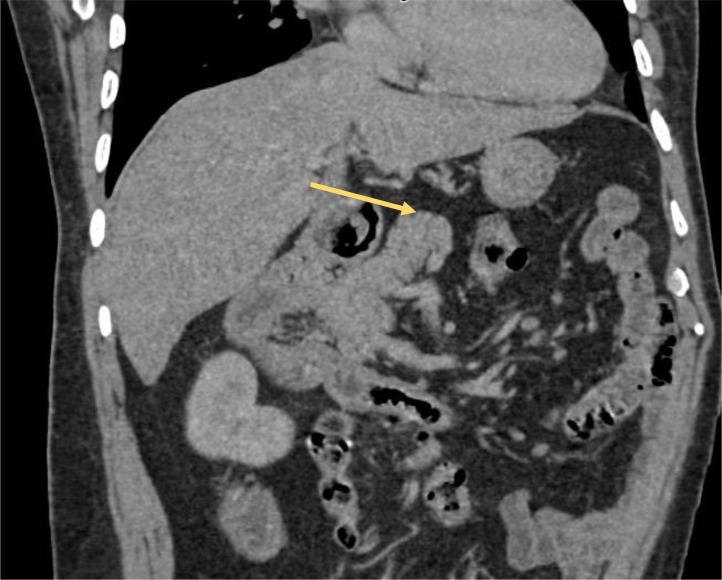

Hemiazygos continuation of a left-sided inferior vena cava (IVC) is an extremely rare developmental anomaly. We present the case of a male patient in whom this condition was incidentally discovered during a thoraco-abdominopelvic CT scan. With the widespread use of contrast-enhanced computed tomography and magnetic resonance angiography, the detection of congenital IVC anomalies has become more accessible. These anomalies are often found incidentally during imaging performed for other clinical reasons. Awareness of this anomaly is crucial before any surgical or endovascular procedures to avoid potential complications.

左侧下腔静脉(IVC)半奇静脉延续是一种极其罕见的发育异常。我们报告一例男性患者,该病症在胸腹部盆腔CT扫描时被偶然发现。随着增强计算机断层扫描和磁共振血管造影的广泛应用,先天性IVC异常的检测变得更加容易。这些异常常在因其他临床原因进行的成像检查中偶然发现。在进行任何外科手术或血管内介入手术之前,认识到这种异常对于避免潜在并发症至关重要。